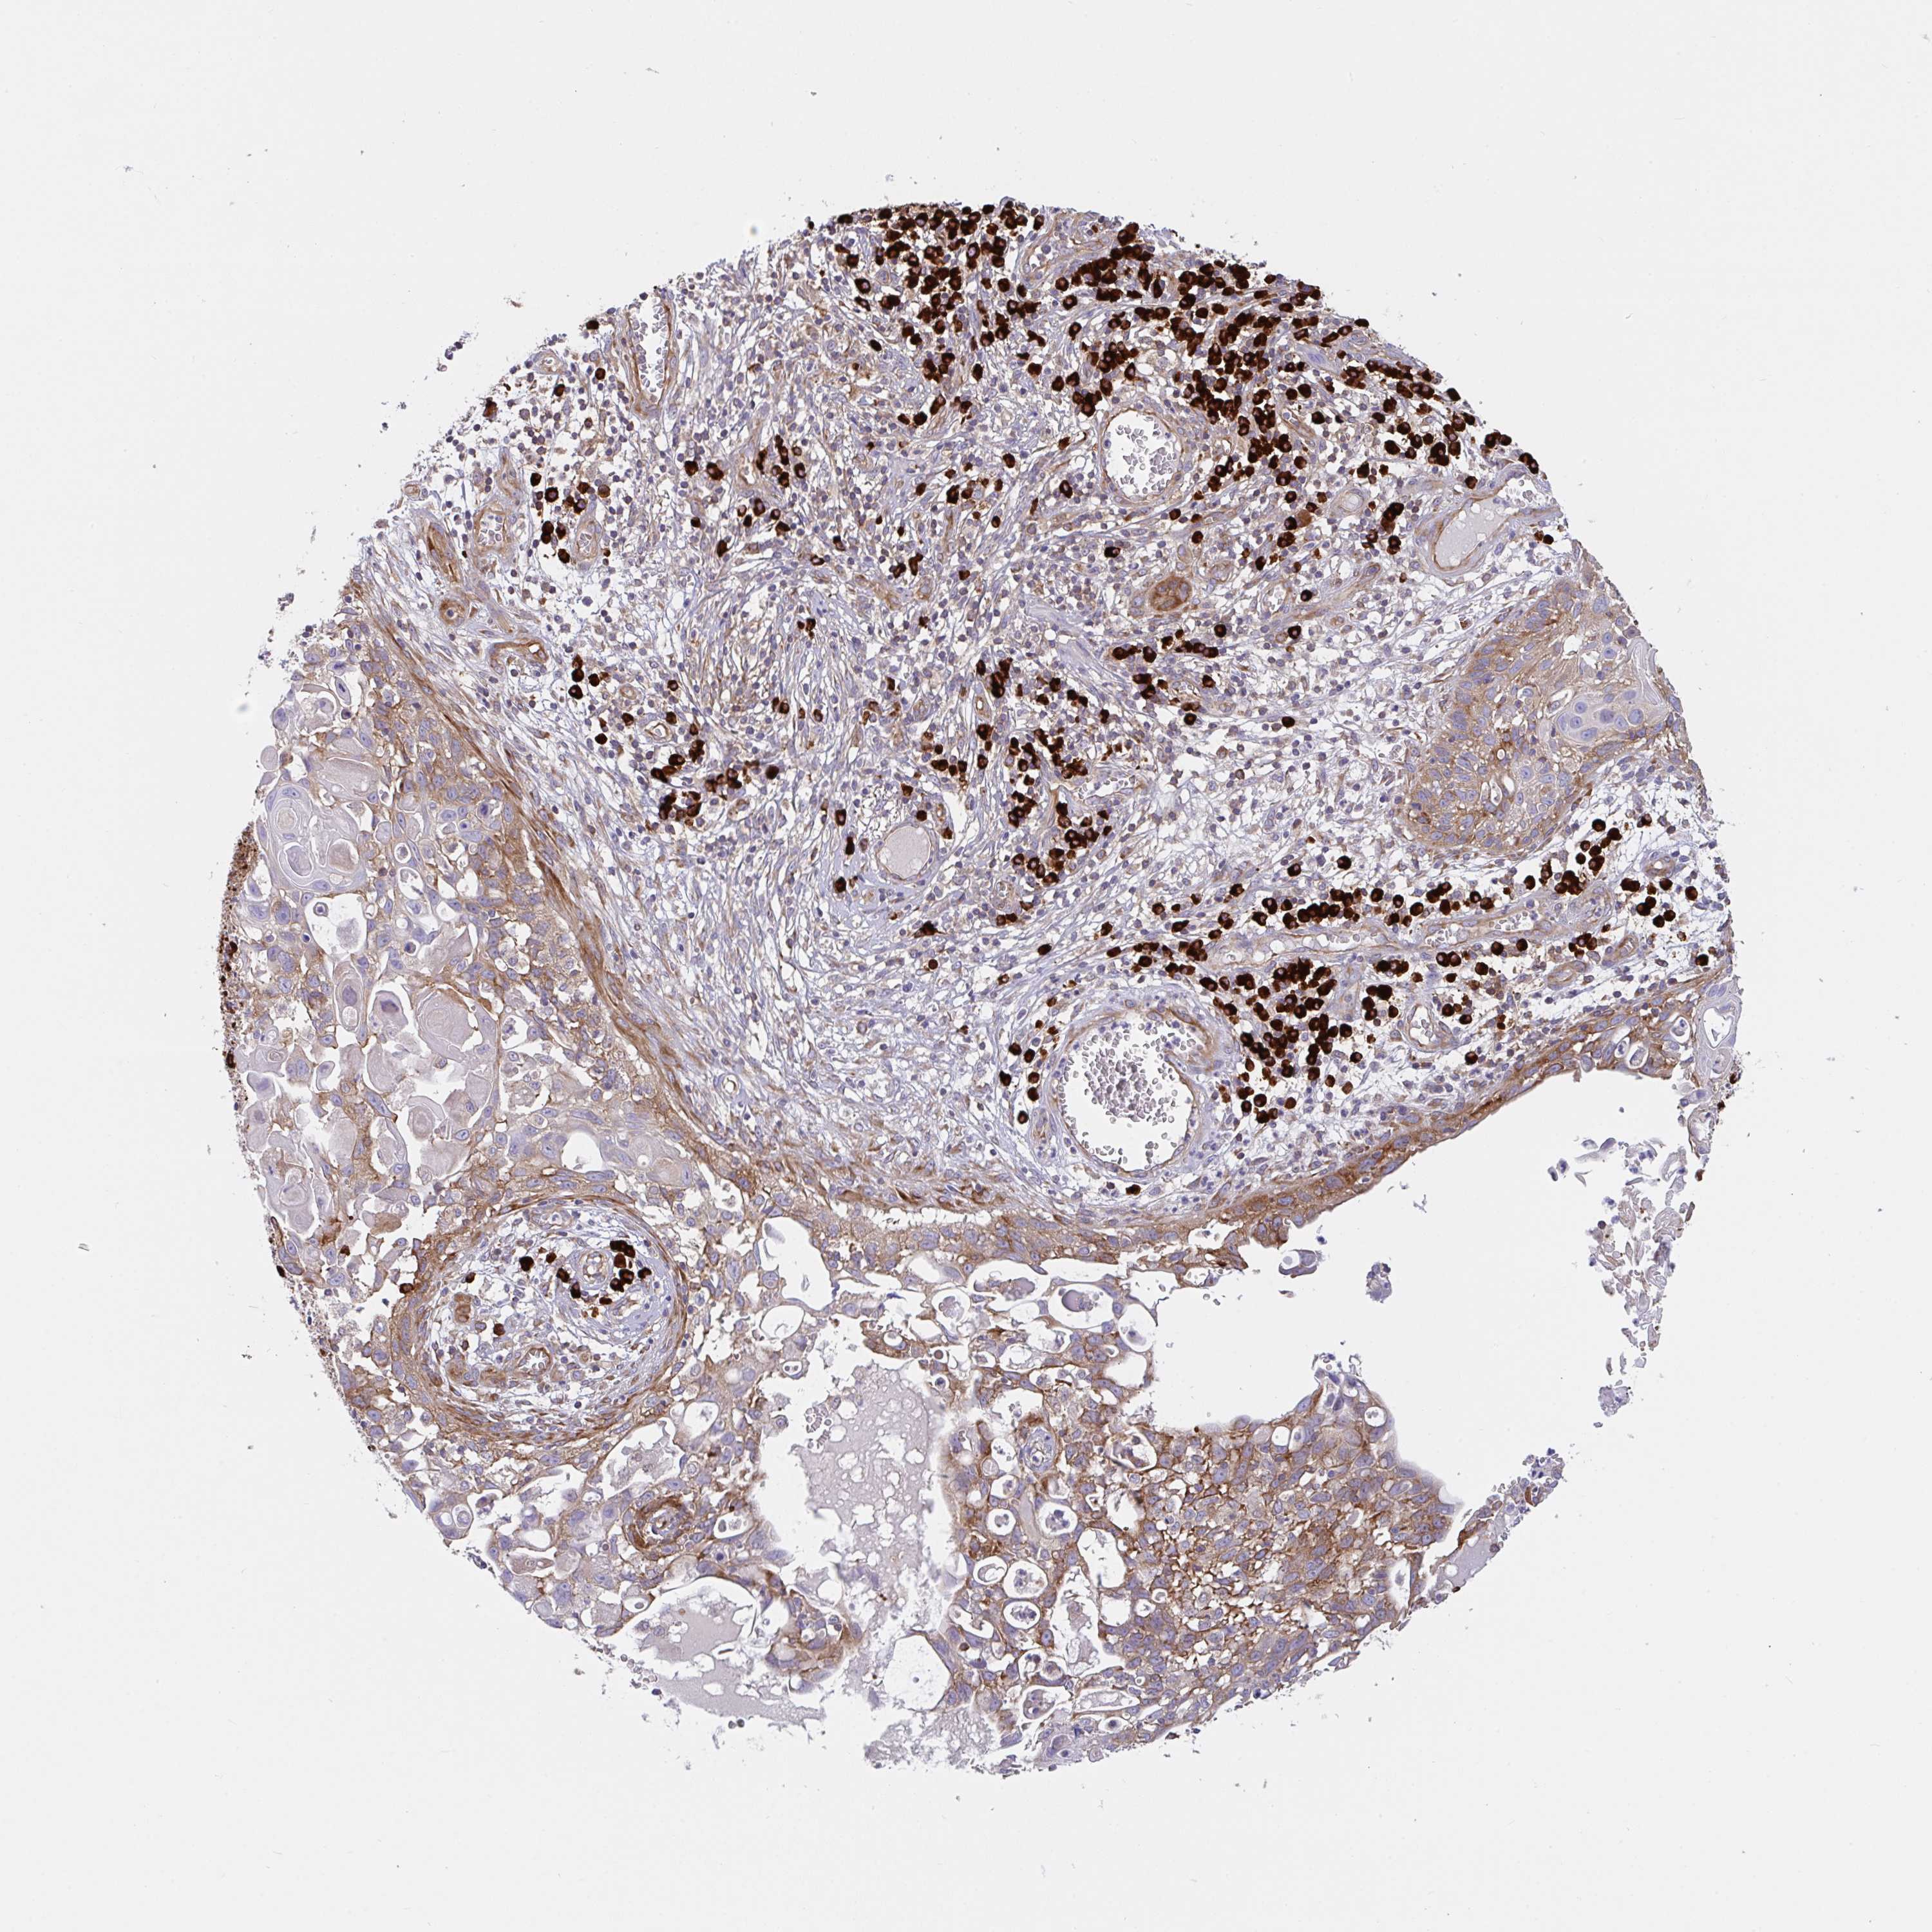

SKIN CANCER - Protein expressioni

A mouse-over function shows sample information and annotation data. Click on an image to view it in a full screen mode. Samples can be filtered based on level of antibody staining by selecting one or several of the following categories: high, medium, low and not detected. The assay and annotation is described here.

Antibody stainingi

Antibody staining in the annotated cell types in the current human tissue is reported as not detected, low, medium, or high, based on conventional immunohistochemistry profiling in selected tissues. This score is based on the combination of the staining intensity and fraction of stained cells.

Each image is clickable and will lead to virtual microscopy that enables deeper exploration of all samples and also displays staining intensity scores, fraction scores and subcellular localization as well as patient and tissue information for each sample.

Antibody HPA038721

Basal cell carcinoma